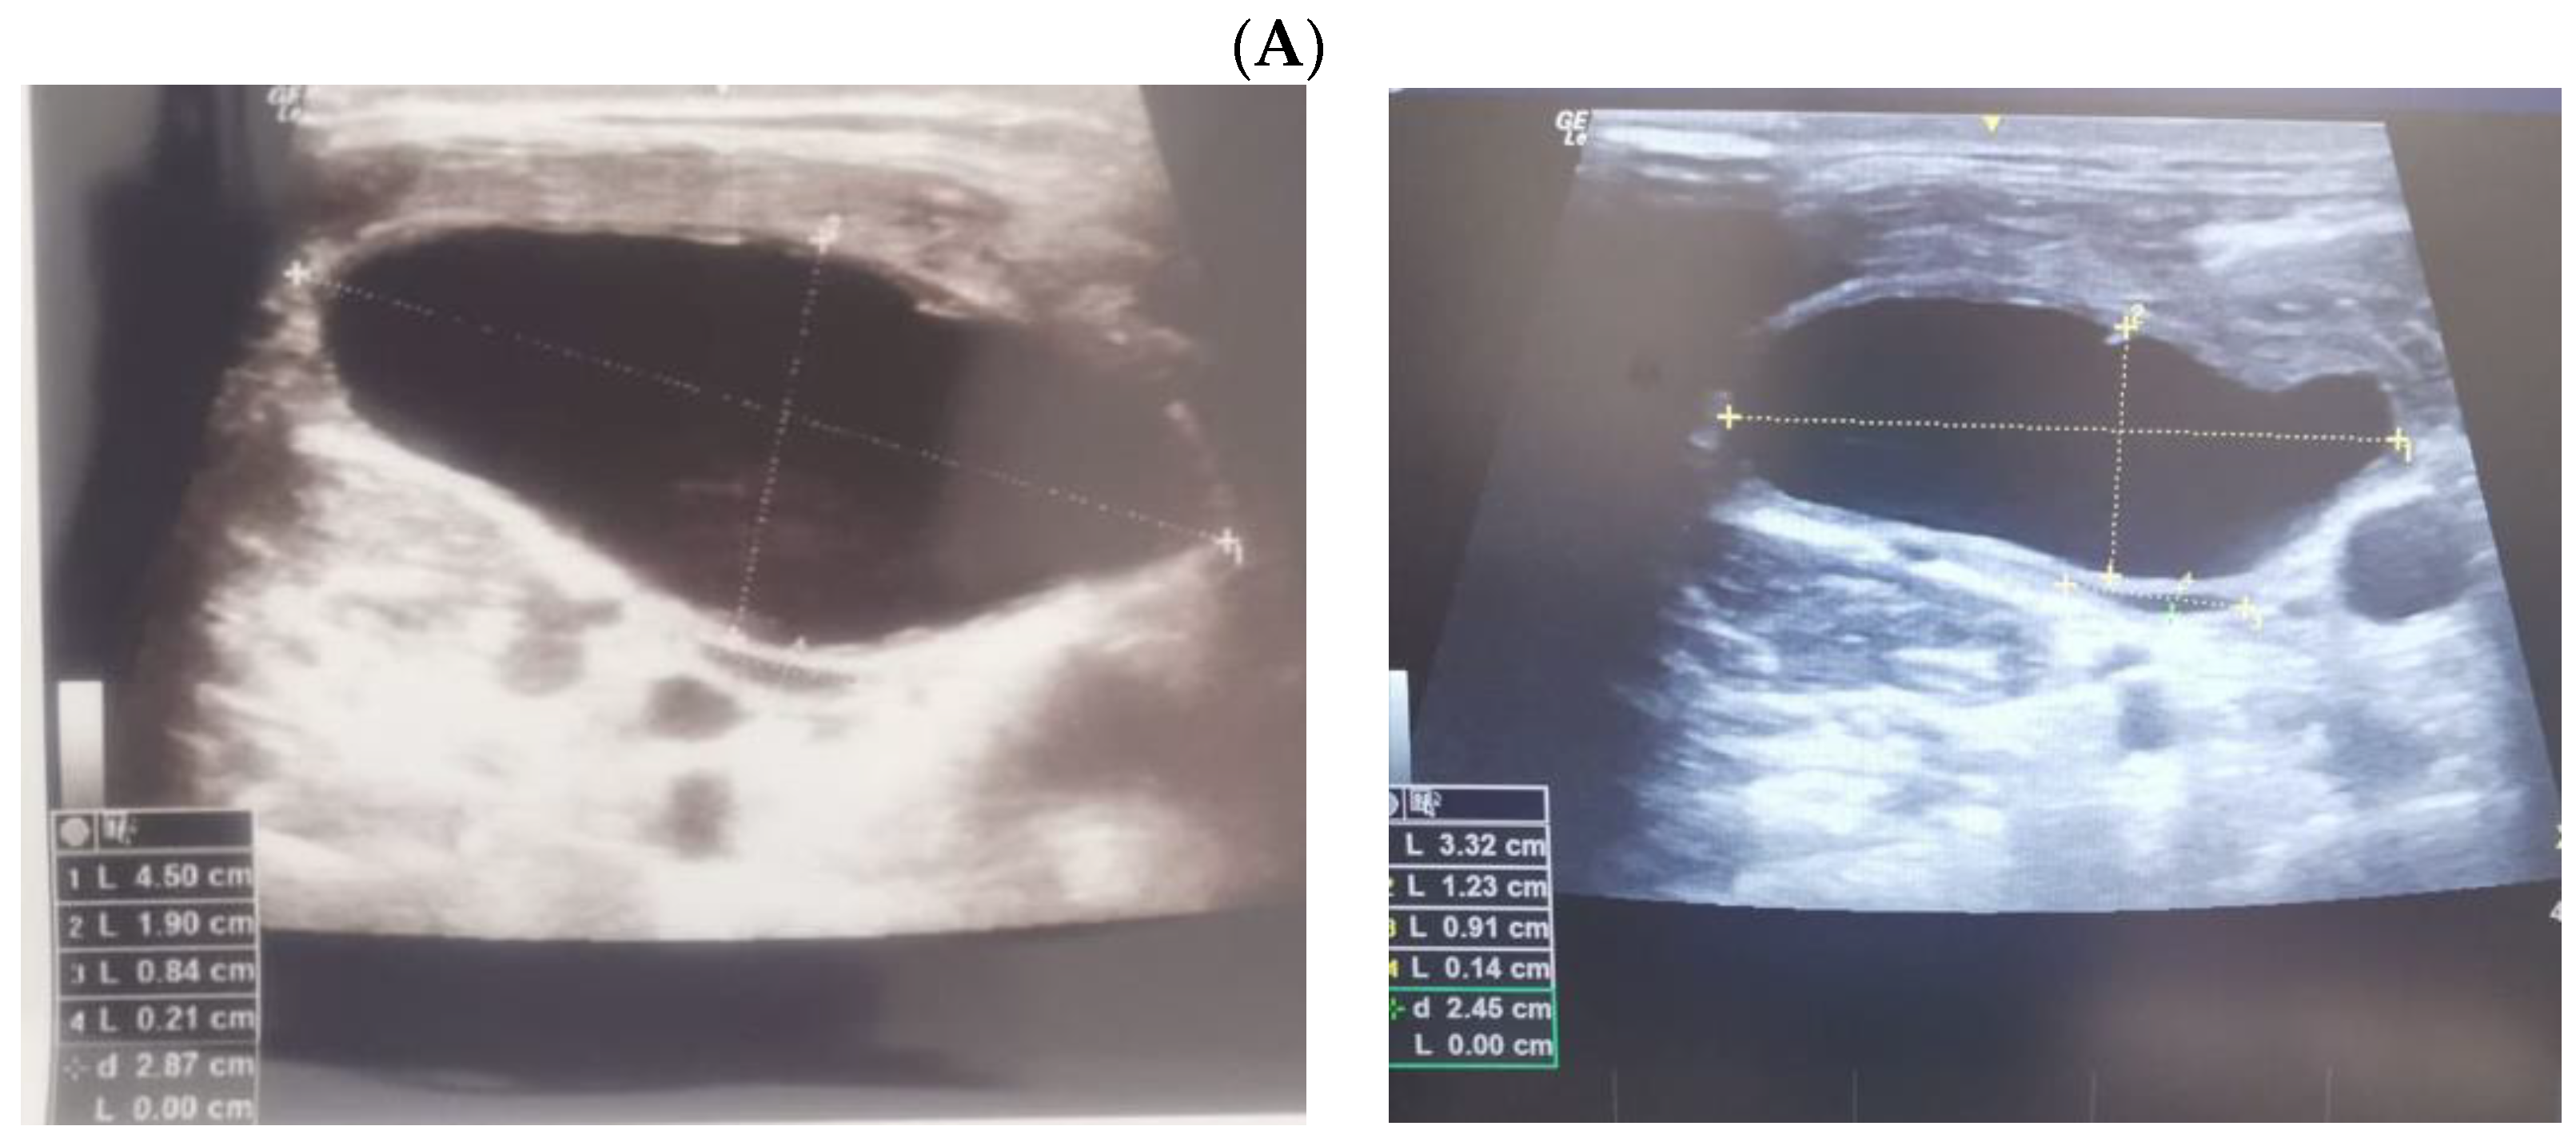

3.2. Thyroidectomy/Lymph Nodes Dissection and Lymphocele/Chylous Leakage

3.3. Post-Thyroidectomy HS and Lymphocele